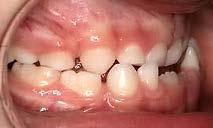

de las aparatologías adecuadas para preservar o en su caso, recuperar el espacio, considerando la edad del paciente y la complejidad del caso a tratar37,38 (Figura 25).

Figura 25.

Caries y pérdida dental

La formación de caries en la dentición decidua y la consecuente pérdida prematura de órganos dentales deciduos, en algunas ocasiones, son

consideraciones a tomar muy en cuenta como factor etiológico en la inclusión del canino (Figura 32).